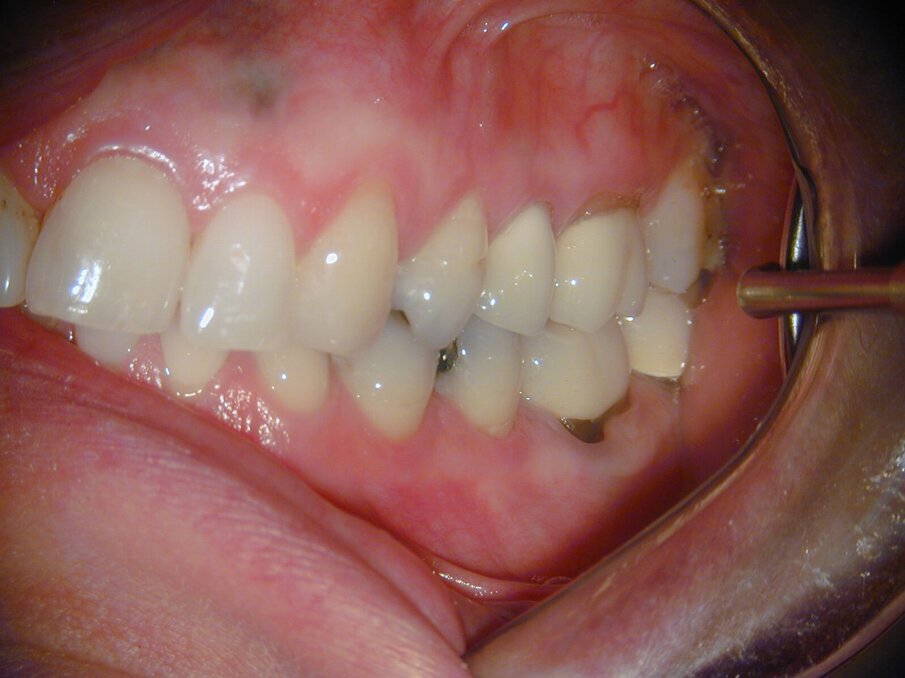

De laatste röntgenfoto en klinische foto’s laten een 37-jarige follow-up zien, waarbij op te merken valt dat ook de amalgaam vullingen 37 jaar geleden werden gelegd (afb. 8-11). De patiënt is volledig klachtenvrij en nog steeds tevreden met het tandheelkundige werk in haar mond.

Afb. 9-11: Klinische foto’s van de 37-jarige follow-up